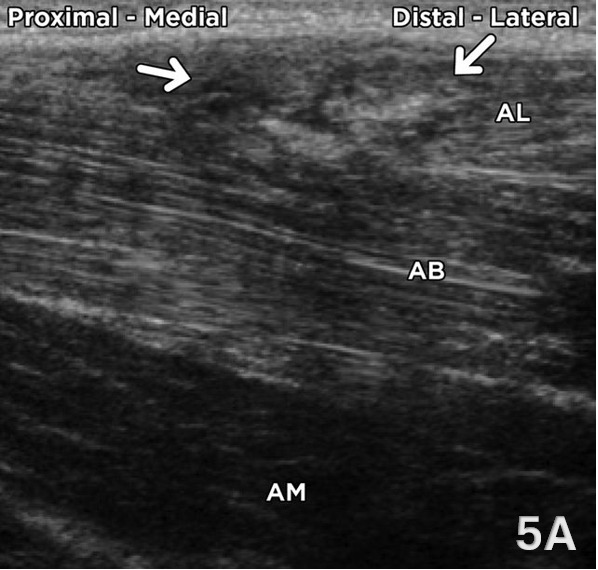

Figure 5. Partial Adductor Longus Muscle Tear in LAX

Figure 5A shows a partial adductor longus muscle tear in a 22-year-old male tennis player presenting with an acute tearing sensation in the right inguinal region. A longitudinal oblique ultrasound image of the proximal adductor compartment demonstrates focal heterogeneity, architectural distortion, and fiber discontinuity within the adductor longus (AL), consistent with a partial muscle tear. The adductor brevis (AB) and adductor magnus (AM) appear intact and maintain normal echotexture and architecture.12